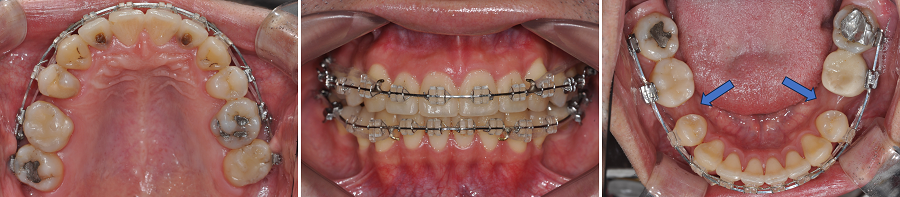

치료 결과 — 교합과 배열이 동시에 개선됨

높은 위치에 있던 상악 양측 견치가 제자리로 배열

✔ 하악 대구치 후방이동 + 직립 완료

전방으로 쓰러져 있던 하악 제1대구치가 완전히 직립되고 후방으로 이동한 덕분에,

이후 보철(크라운) 제작 시 치근 방향과 일치하는 형태로 제작 가능해졌습니다.

쓰러진 치아가 계속 교합압을 받는 경우 치아에 좋지 않은 영향을 줄 수 있으므로, 이러한 치아의 직립은 큰 의미가 있습니다.

✔ 상악 우측 제2소구치 발치공간 폐쇄와 상악 좌측 구치 후방이동을 통한 구치 관계 안정화

전반적인 치열의 흐름이 정상궤도로 회복되었습니다.

환자분의 일정에 맞추어 치료를 종료하다보니, 정중선을 완벽히 맞추지 못한 점이 아쉽습니다.